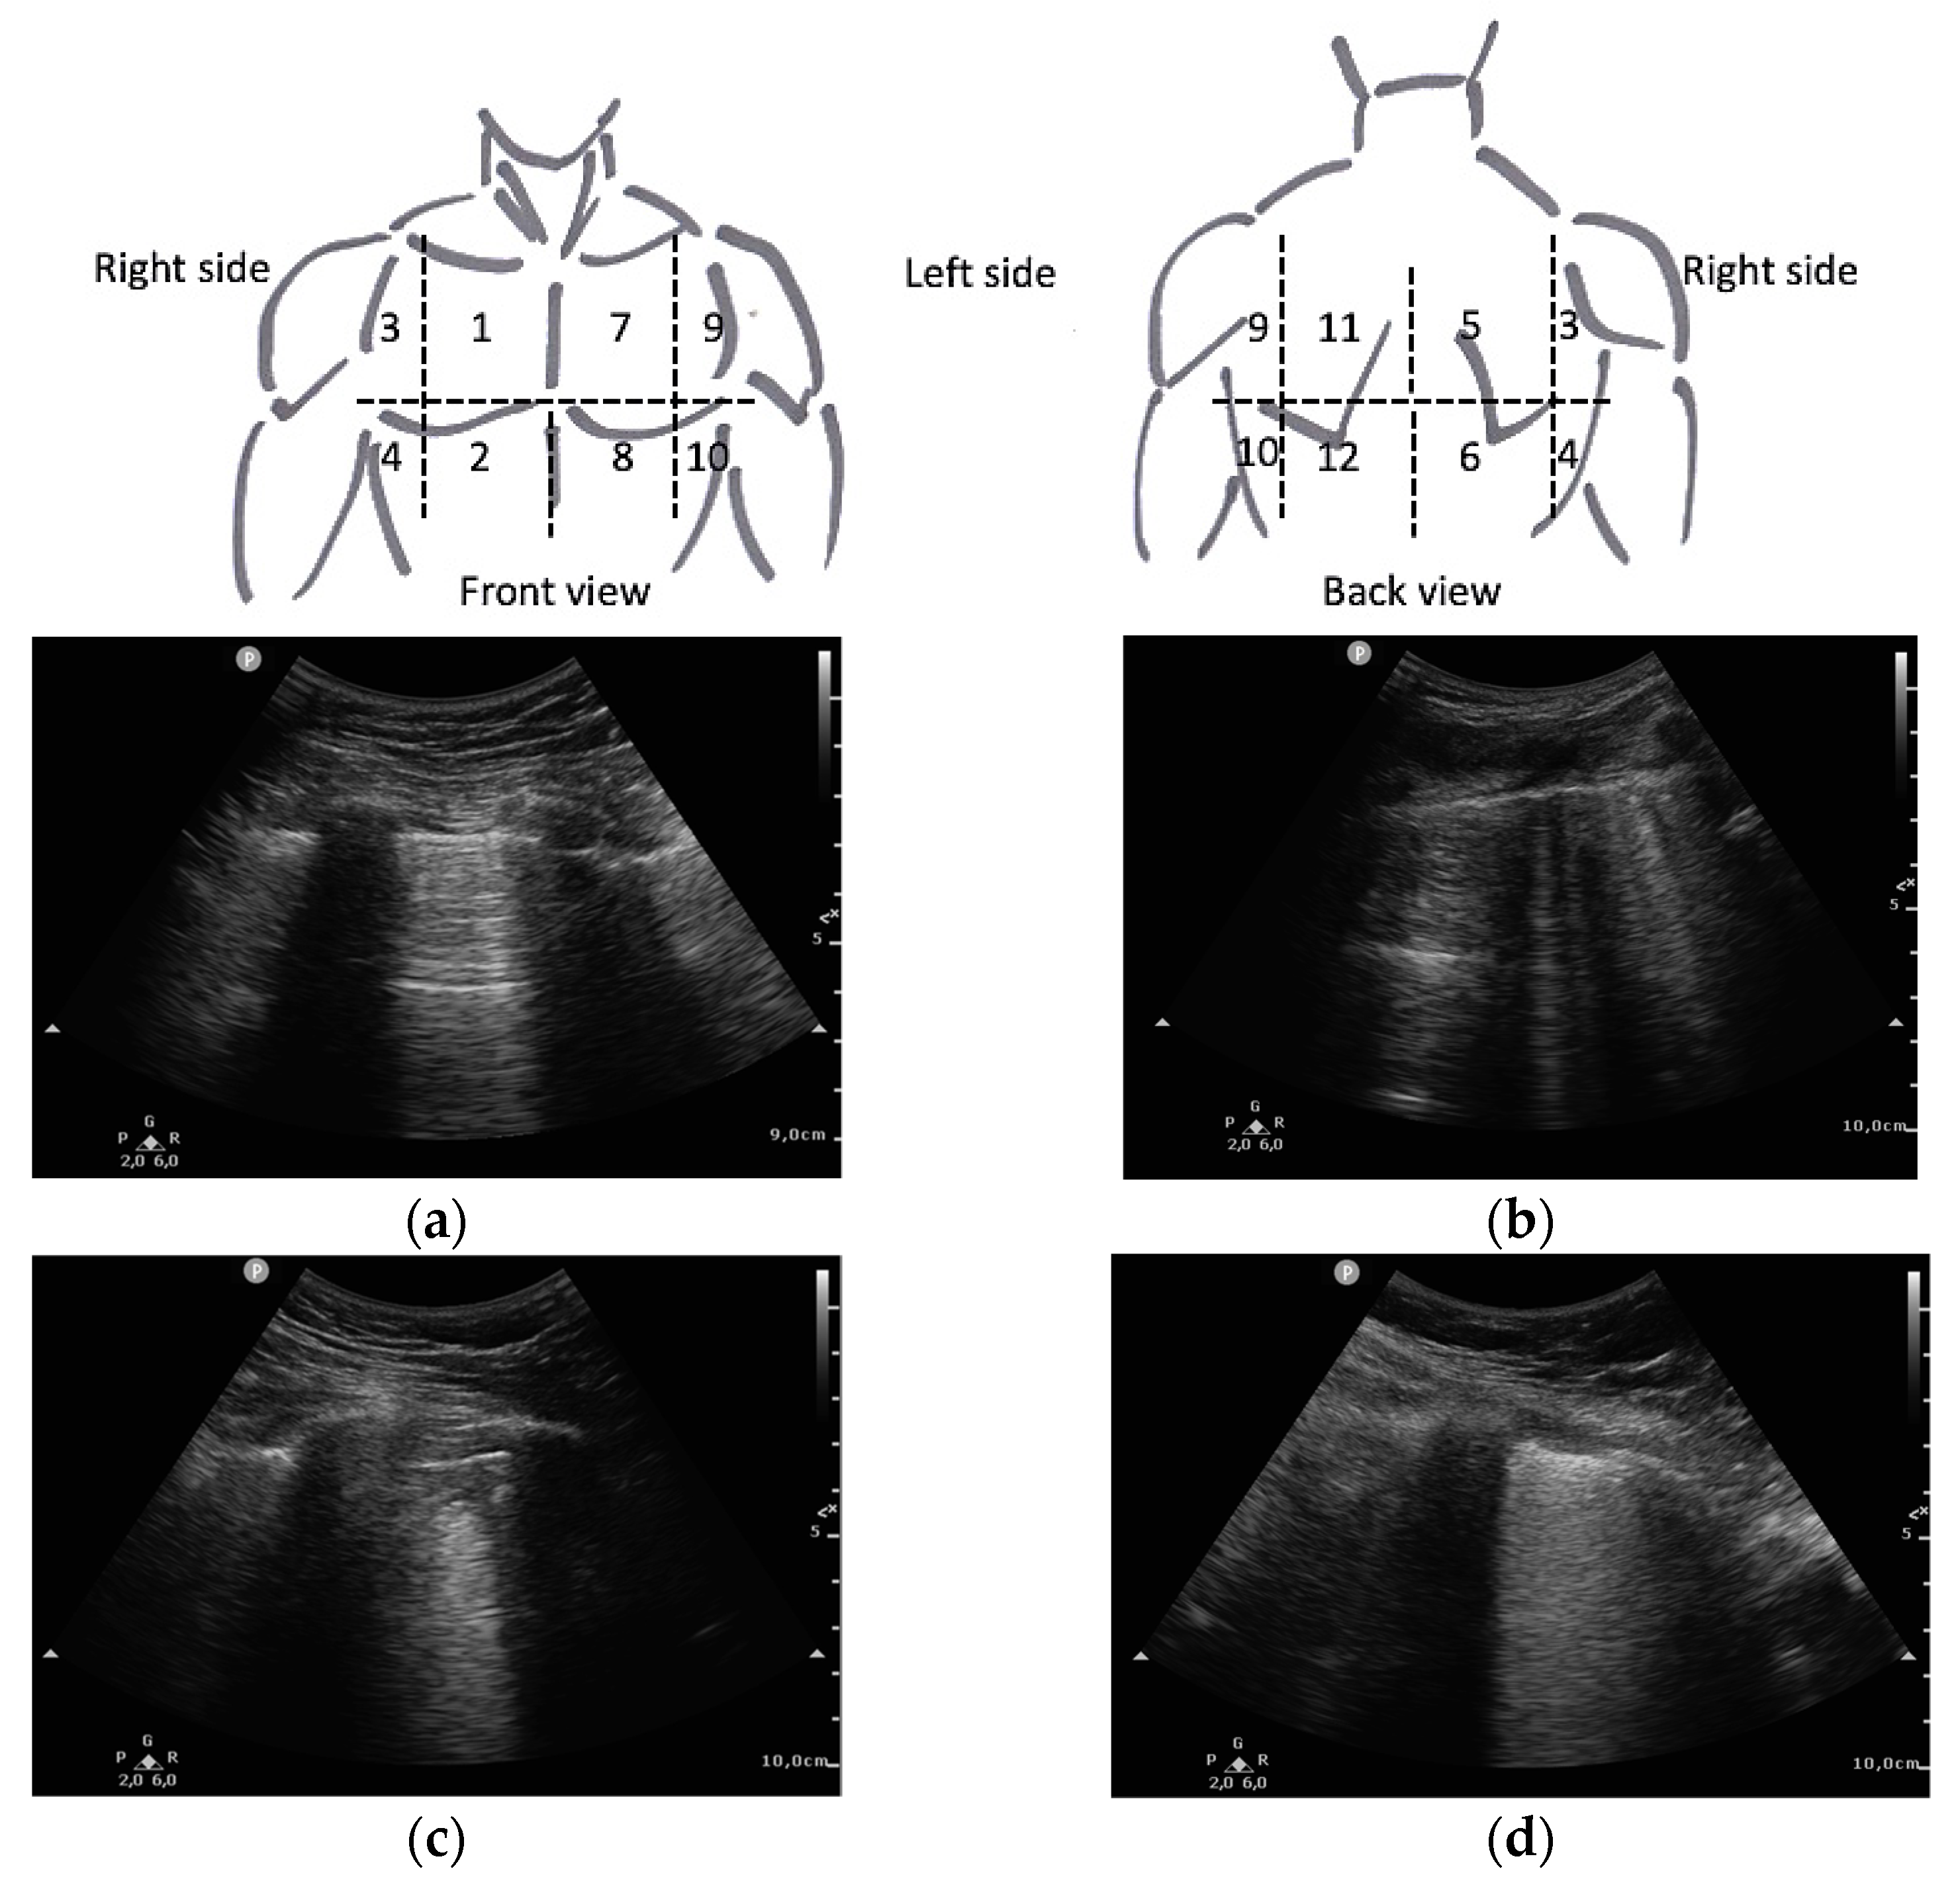

Ultrasound imaging was performed with an ultrasound scanner PHILIPS® SPARQ (Koninklijke Philips N. V.; Amsterdam, The Netherlands). The predefined lung programme was established, using a convex transducer 6–2 MHz. The Clinical Care Ultrasound Group of the hospital trained 6 Internal Medicine physicians in lung ultrasound, who obtained the images. At least 2 examiners were present when the ultrasound images were acquired in order to reduce the inherent inter-individual variability in this technique. We used a 12 lung fields protocol, as it is the protocol that has shown the best balance between accuracy and acquisition time [17]. The clavicular midline and paravertebral line divided each hemithorax into anterior, lateral, and posterior fields. These fields were further subdivided into superior and posterior fields, resulting in 6 fields in each lung (Figure 1). Prior examination of the patients medical history was avoided to prevent possible biases in image acquisition.

Figure 1.

Lung areas distribution and LUS score as described by Soldati et al. [7]: (a) 0 points (normal A-lines pattern); (b) 1 point (>3 B-lines); (c) 2 points (subpleural consolidation); (d) 3 points (pulmonary consolidation or “with lung”).

Furthermore, the most widely recognised international index for lung ultrasound in COVID-19 is the Lung Ultrasound Score (LUS) [11]. It scores from 0 to 3 each of the fields analysed, depending on the severity of the findings in each of them, as shown in Figure 1. The final sum of the score for all fields is used as a prognostic value. It was developed only correlating the score with clinical severity [7].